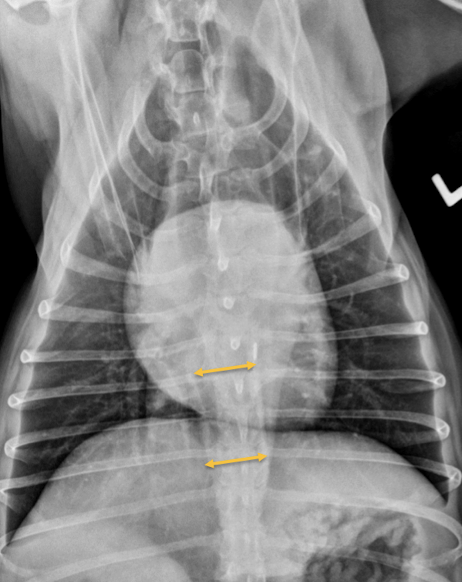

A

Esophageal dilation